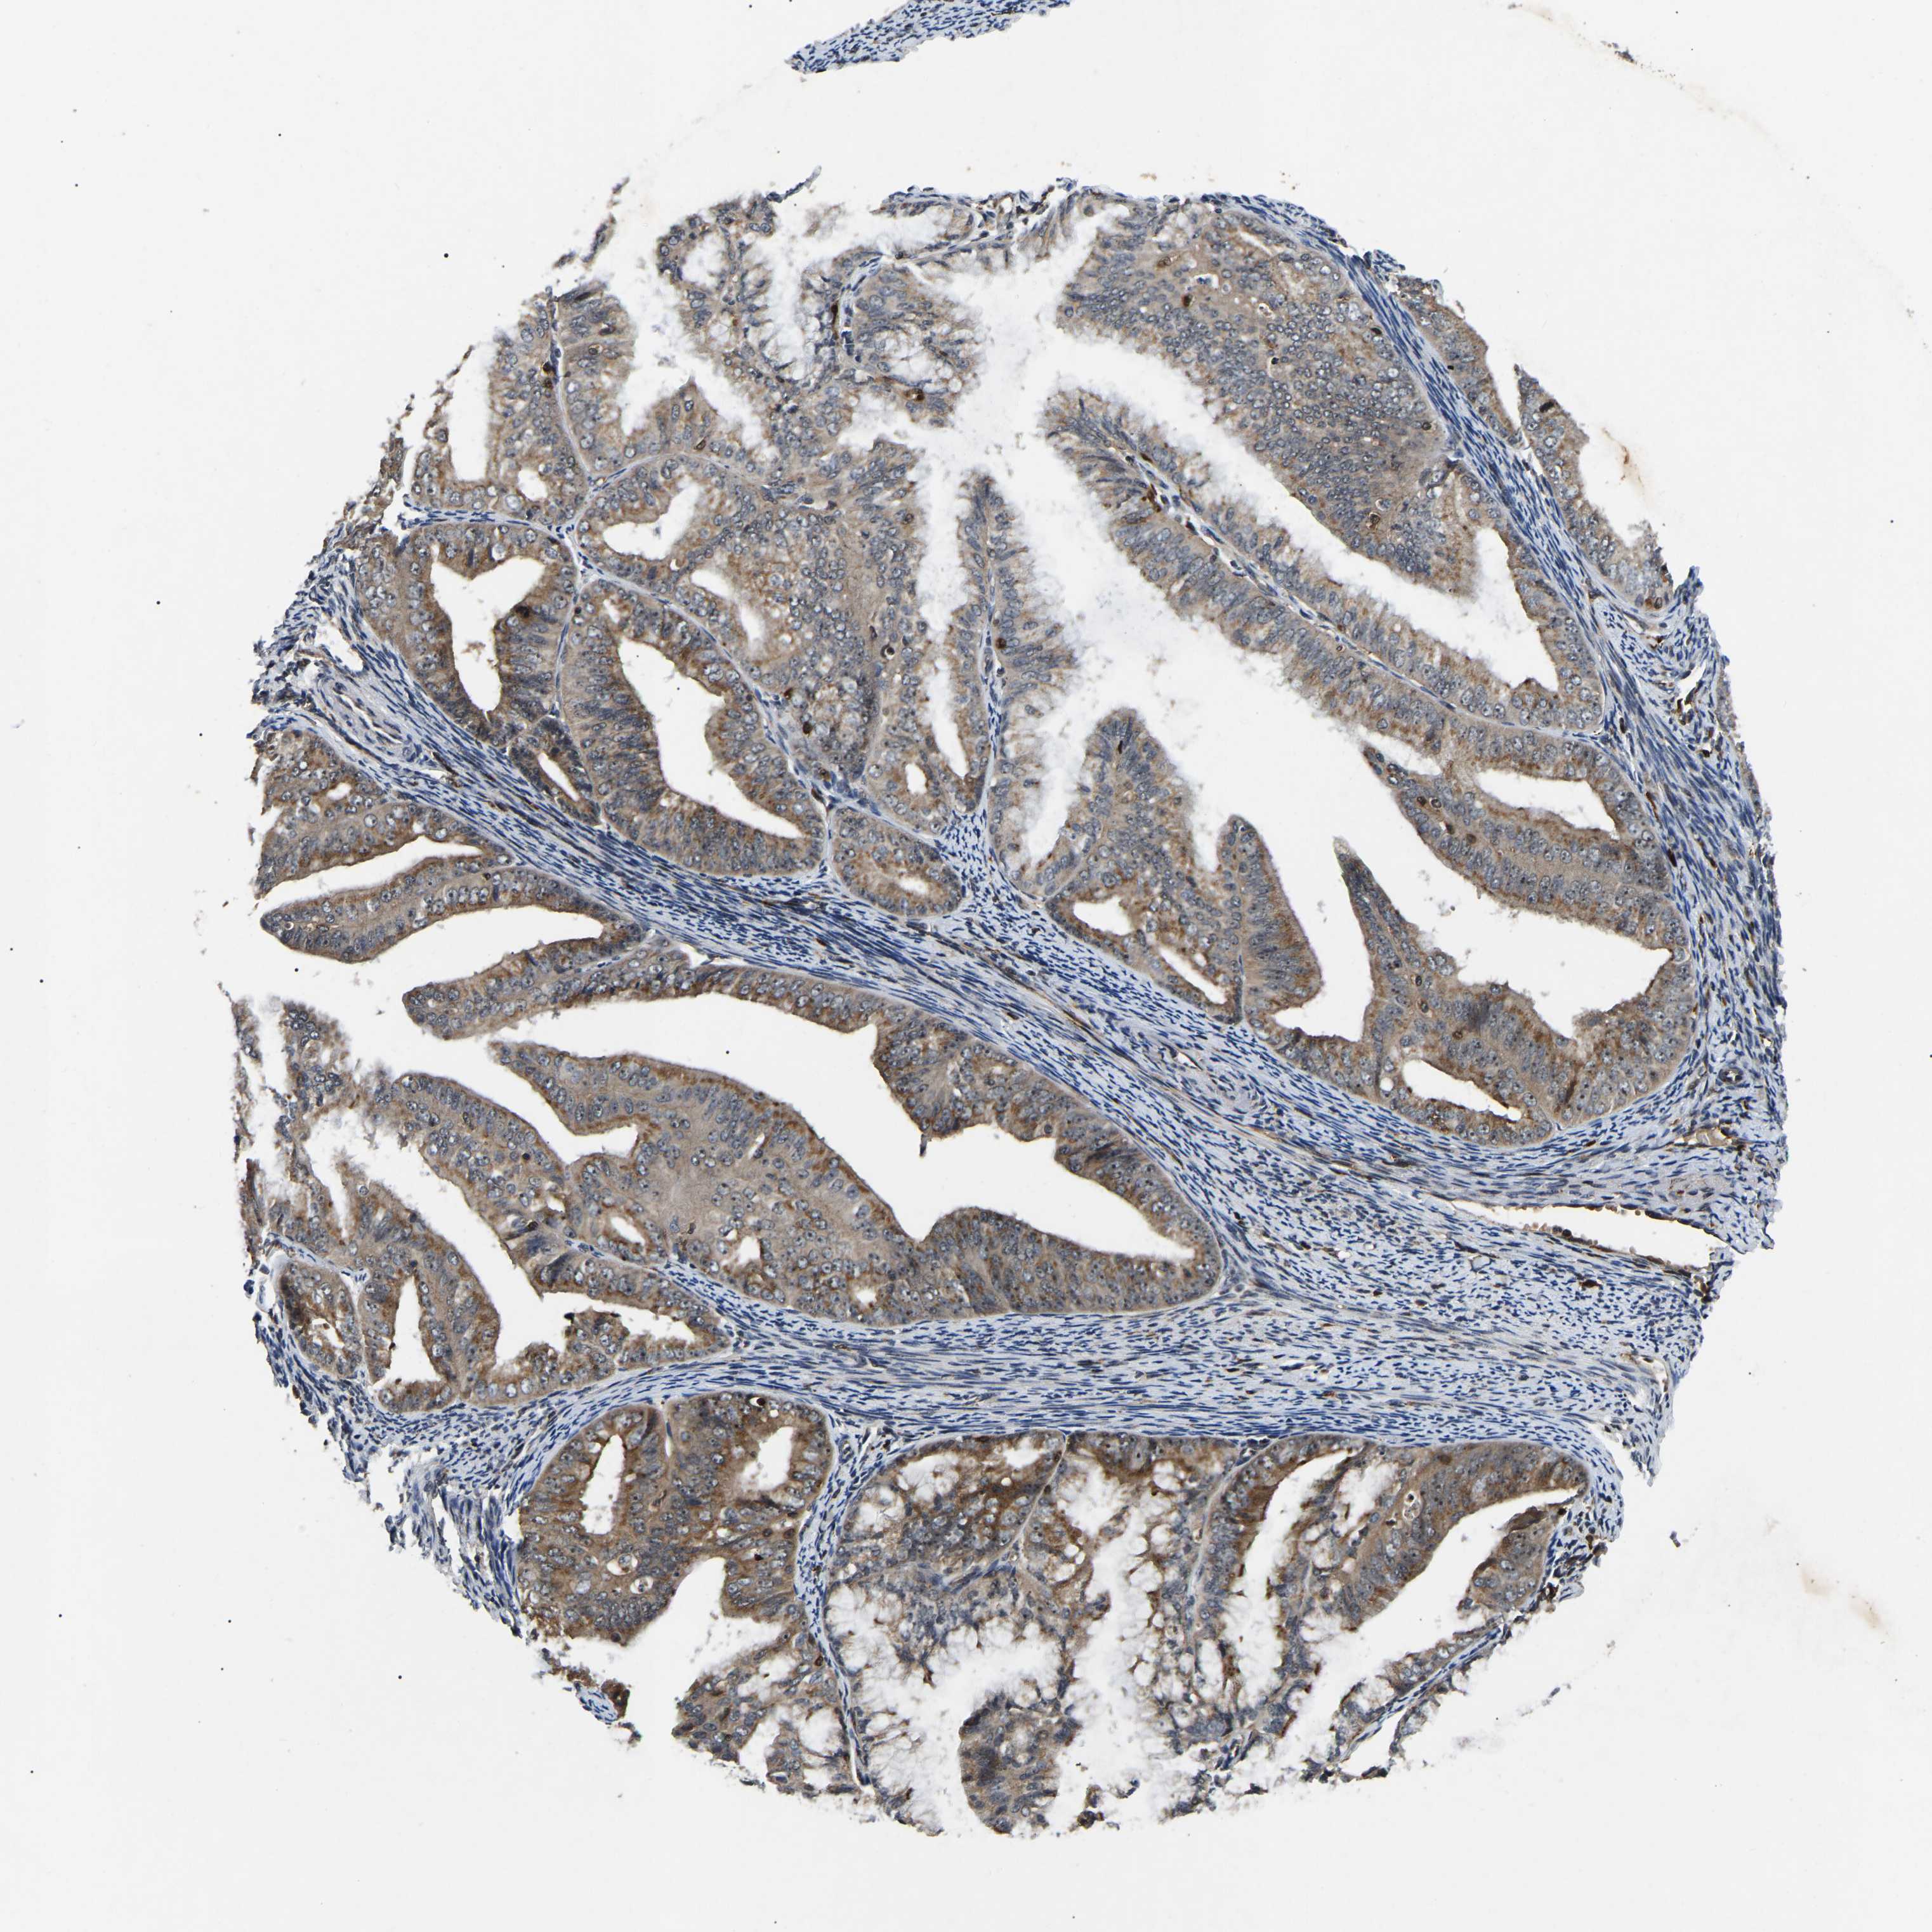

ENDOMETRIAL CANCER - Protein expressioni

A mouse-over function shows sample information and annotation data. Click on an image to view it in a full screen mode. Samples can be filtered based on level of antibody staining by selecting one or several of the following categories: high, medium, low and not detected. The assay and annotation is described here.

Note that samples used for immunohistochemistry by the Human Protein Atlas do not correspond to samples in the TCGA dataset.

Antibody stainingi

Antibody staining in the annotated cell types in the current human tissue is reported as not detected, low, medium, or high, based on conventional immunohistochemistry profiling in selected tissues. This score is based on the combination of the staining intensity and fraction of stained cells.

Each image is clickable and will lead to virtual microscopy that enables deeper exploration of all samples and also displays staining intensity scores, fraction scores and subcellular localization as well as patient and tissue information for each sample.

Antibody HPA019058

Antibody HPA026672

Staining

High

Medium

Low

Not detected

Intensity

Strong

Moderate

Weak

Negative

Quantity

>75%

75%-25%

<25%

None

Location

Nuclear

Cytoplasmic/membranous

Cytoplasmic/membranous,nuclear

Adenocarcinoma, NOS